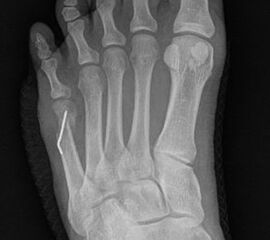

Abb. 3a, b: Präoperatives (a) und postoperatives (b) Röntgenbild bei Korrektur einer Typ I Deformität durch eine Exostosenabtragung.